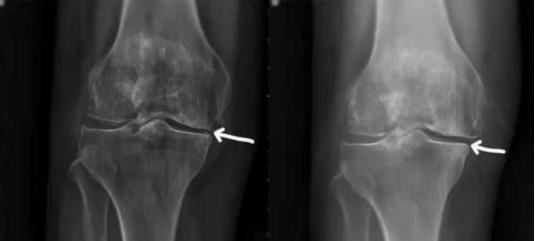

治疗效果: PRP治疗半年后,膝关节平片检查结果显示,膝关节内侧缘间隙明显增宽。Lysholm膝关节评分90分,VAS疼痛评分1分(偶尔)。目前随访1年余,患者恢复良好。